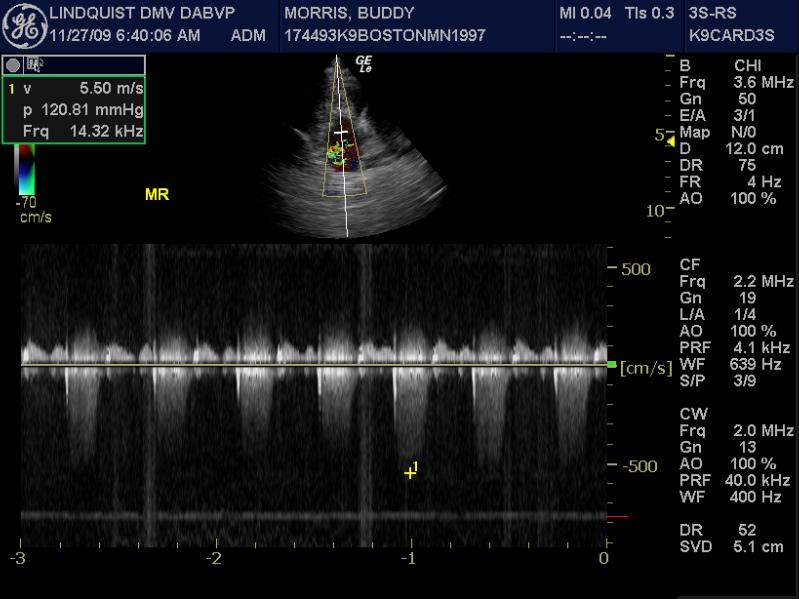

A 10-year-old neutered male Boston Terrier dog was presented for possible seizure activity. A grade II/VI heart murmur and left submandibular lymphadenomegaly were present on physical examination. Abnormalities on CBC and blood chemistry included neutrophilia, eosinopenia, thrombocytosis, elevated ALP activity, and elevated CK. T4 was within normal limits. The patient was treated with enalapril and clindamycin pending ultrasound.